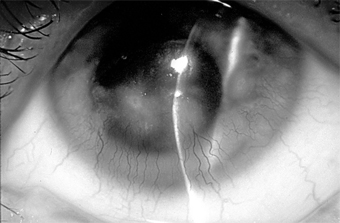

Figure 5-17

Figure 5-17: Skin lesions in acne rosacea. (Courtesy of HB Ostler.)

Treatment of ocular rosacea consists of the elimination of hot, spicy foods and of alcoholic beverages that cause dilation of the facial vessels. Any secondary staphylococcal infection should be treated (Figure 5-18). A course of oral tetracycline or doxycycline is often helpful, and a smaller maintenance dose may be needed to control the disease.

Figure 5-18

Figure 5-18: Multiple concretions on the inferior tarsus. These are often associated with chronic lid disease caused by staphylococcal species.